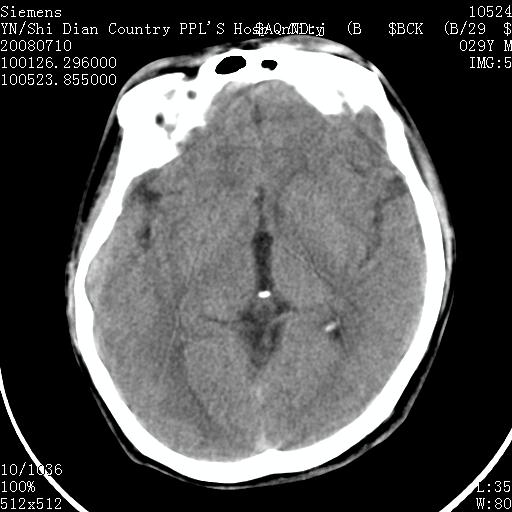

以下是引用随光逐影在2008-7-10 15:19:00的发言:[br]1)考虑左侧尾状核钙化。2)透间隔间腔与vergae腔并存。

以下是引用卜一在2008-7-10 16:43:00的发言:[br]1)考虑左侧尾状核钙化。2)透间隔间腔形成。支持!